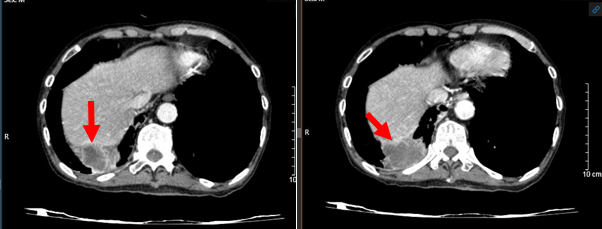

- Hình ảnh chụp cắt lớp vi tính ngực – bụng (15/03/2024):

Hình 2: Hình ảnh chụp cắt lớp vi tính ngực – bụng: U thùy dưới phổi phải xâm lấn gan (mũi tên đỏ).

Kết luận: Hình ảnh khối u vị trí rốn phổi phải và thùy dưới phổi phải, xâm lấn nhĩ trái gây huyết khối buồng nhĩ trái, xâm lấn thực quản, cơ hoành, nhu mô gan phải. Nốt đặc rải rác phổi trái, hạch trung thất, nốt tuyến thượng thận trái – theo dõi tổn thương thứ phát. Giãn phế nang rải rác nhu mô phổi 2 bên.